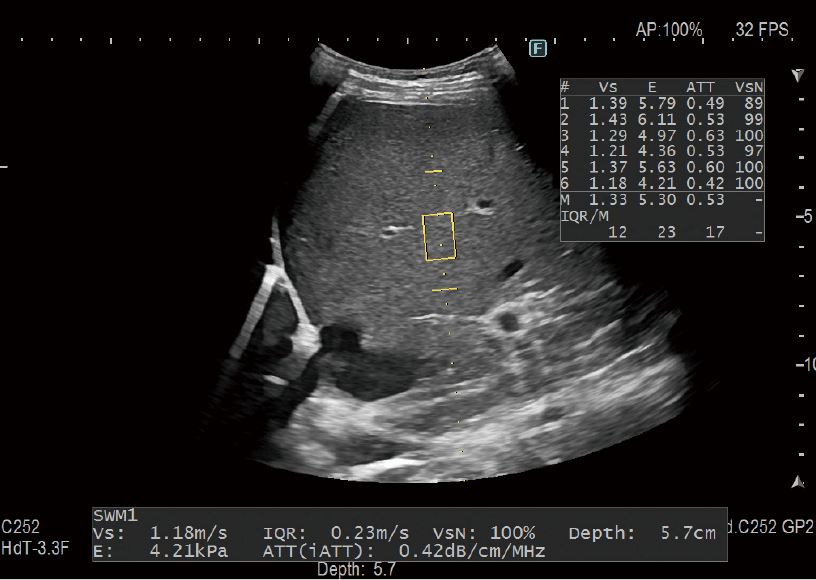

It is possible to evaluate tissue stiffness by generating shear waves and measuring Vs (propagation velocity in tissue). iATT measures an index (ATT) to estimate fatty liver quantification. The narrowing of the analysis area and the guided display make it easy to set the ROI therefore avoiding multiple reflections and structures such as blood vessels that would interfere with ATT measurement.